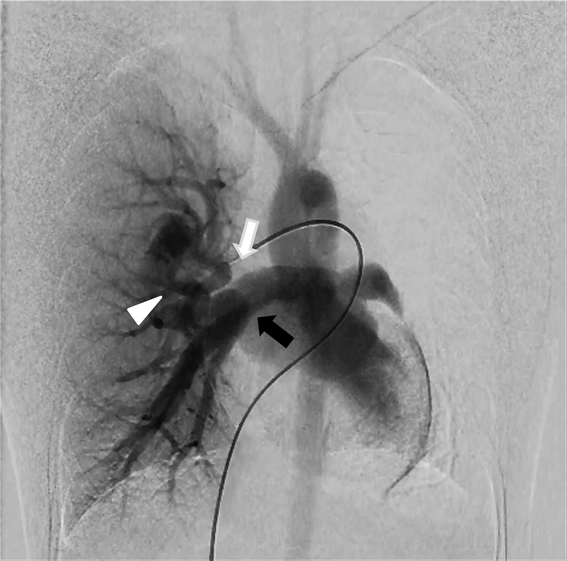

先天性片側肺静脈狭窄に対側のAnomalous Unilateral Single Pulmonary Veinを合併した1例A Case of Congenital Unilateral Pulmonary Vein Stenosis with Contralateral Anomalous Unilateral Single Pulmonary Vein